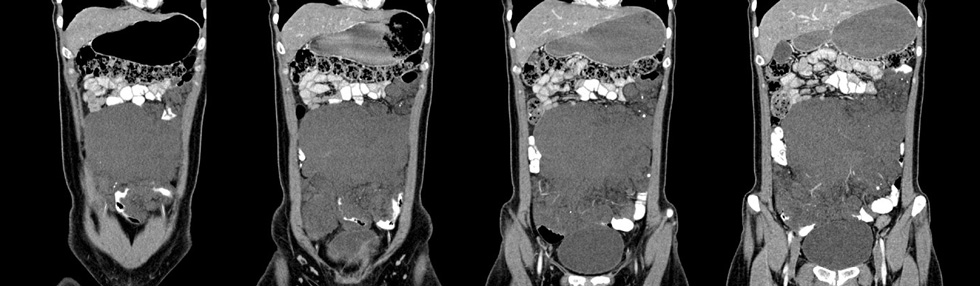

女性,28岁,停经3月,腹部膨隆1月,产前检查发现腹部占位

{肿块中心ct值27hu,增强后,动脉期、门脉期均无明显强化)

患者手术病理:腹腔囊性淋巴管瘤,象这样充满整个腹腔的的确很少见